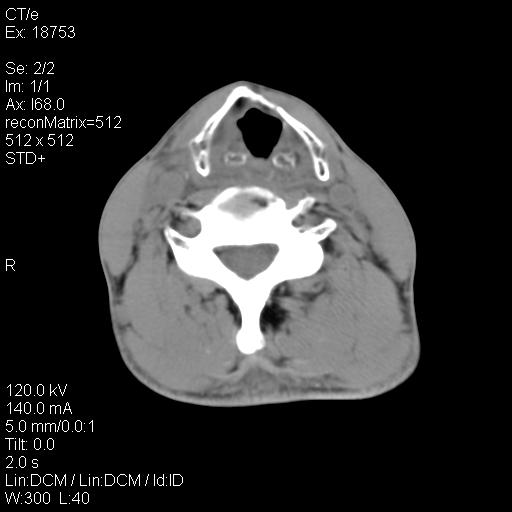

标题: CT21693:男 58岁 右侧咽部疼她2天余 PE:右侧扁桃体肿大 压痛 [打印本页]

标题: CT21693:男 58岁 右侧咽部疼她2天余 PE:右侧扁桃体肿大 压痛

右化脓性扁桃体炎症伴咽后壁脓肿形成.